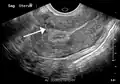

A small uterine fibroid seen within the wall of the myometrium on a cross-sectional ultrasound view -